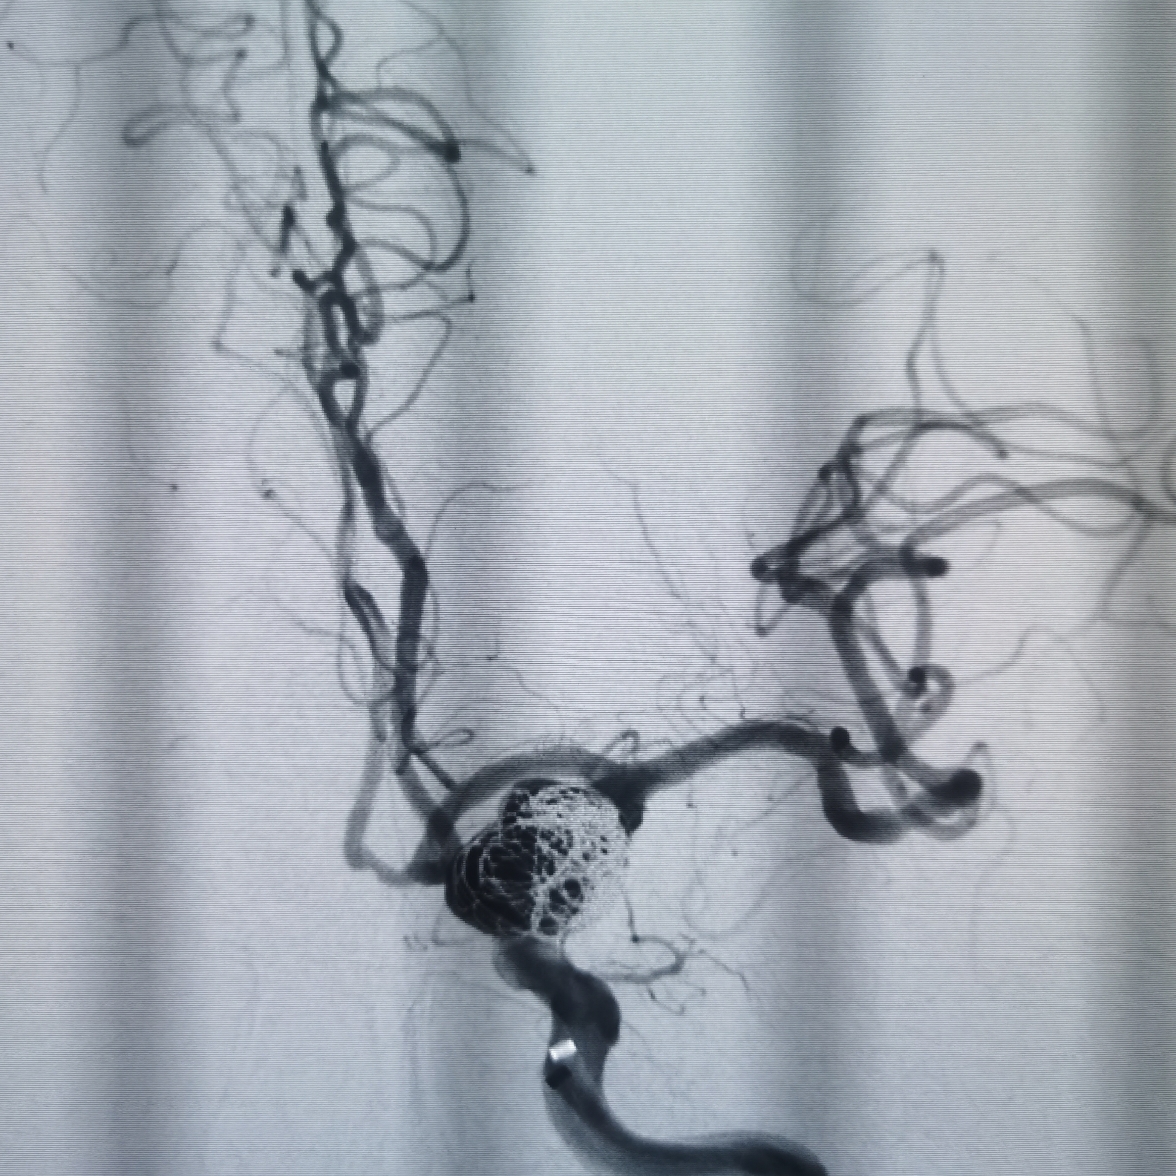

DSA示右侧大脑中动脉M1远端重度狭窄。

左侧颈内动脉C7动脉瘤改变。

微导管塑形后送入动脉瘤腔内,首枚填入12*30成蓝圈,再依次填入10*30,9*30,8*30弹簧圈,造影见瘤体上部致密填塞,载瘤动脉通畅。

利用微导丝将栓塞微导管再重新选入动脉瘤体下部,依次填入7*30,7*20弹簧圈,复查造影见动脉瘤大部填塞,瘤内造影剂滞留明显载瘤动脉通畅。